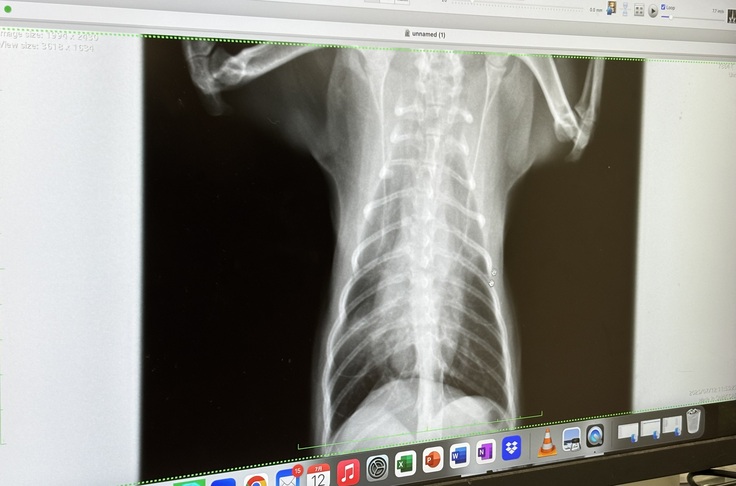

病院での診断は肺挫傷、肋骨骨折、胸骨脱臼でした。左肺が挫傷しているので無気肺になっていたみたいで呼吸がしにくそうでした。呼吸はしているけど意識は朦朧としているのか動く事もなく眠そうにしていました。

↑左肺が酸素が無い無気肺になっています。

右の肋骨が骨折しているのが分かります。